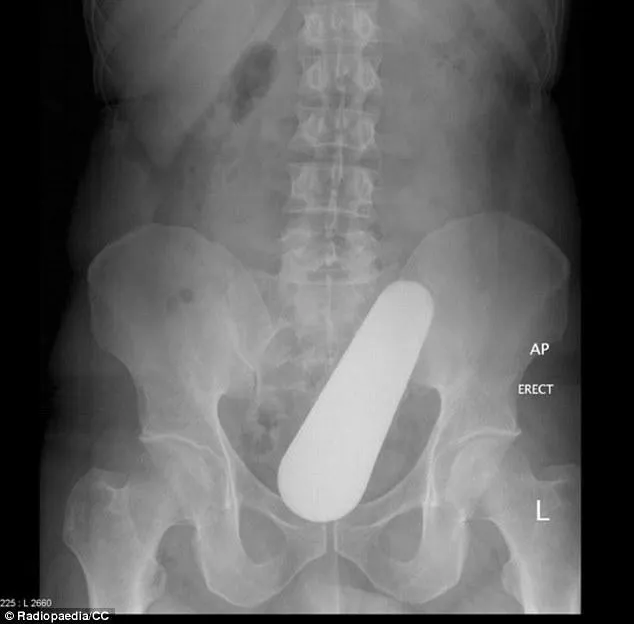

Comment ce pilon est-il arrivé là ? Selon le centre de recherche en radiothérapie Radiopaedia, il aurait pénétré dans le rectum d"un patient de 40 ans "tombé par terre en cuisinant".